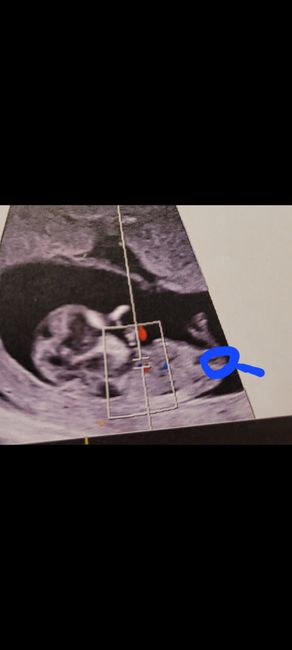

Nub theory, giochiamo un po’Da Anna95 , Il 27 Novembre 2024 alle 22:49

Ciao ragazze, lunedì scorso ho fatto eco genetica a 11+5 ma bebè misurava 12 settimane, ho fatto dna fetale che dovrebbe arrivare questa settimana, ma nel frattempo per...